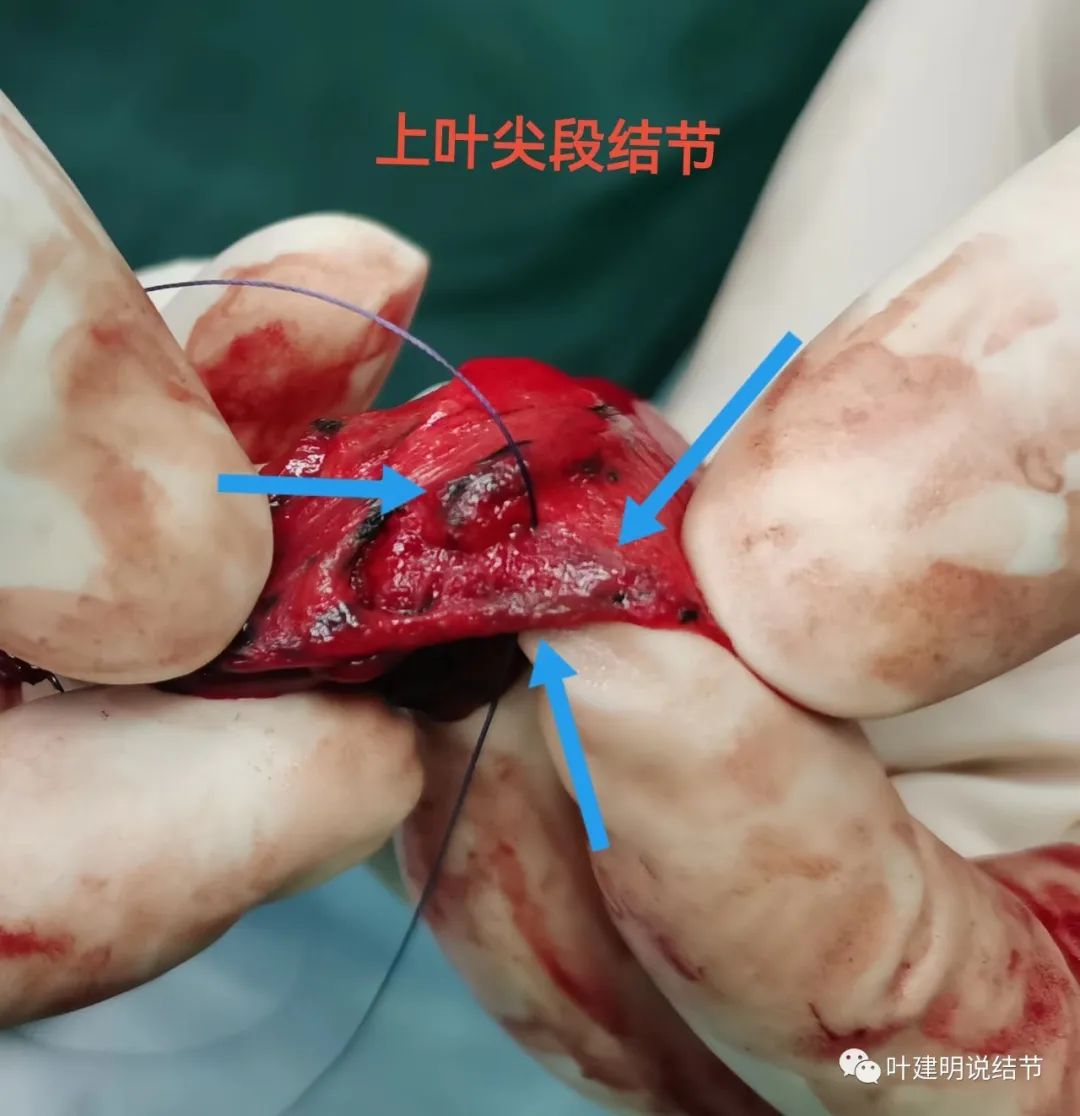

尖段病灶2表面可见,此处略灰白,予以切除。

上叶后段病灶6定位后局部切除。

确实如术前判断,上叶尖段病灶2、后段病灶6与下叶灶8是原位腺癌,中叶病灶9是浸润性腺癌,贴壁占10%,腺泡型占90%。切缘均阴性。